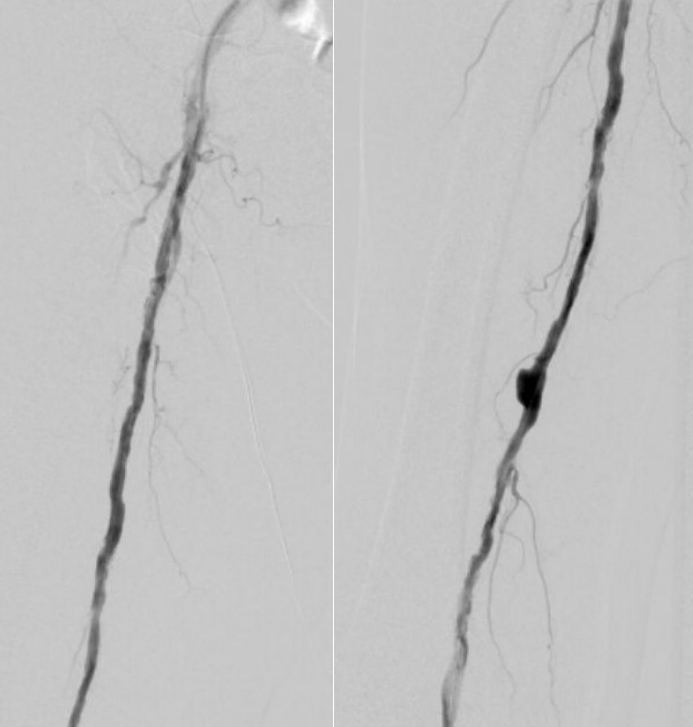

7. 术后造影血流恢复

本例患者股浅动脉重度闭塞,股浅远端重度钙化病变近收肌管,利用Shockwave冲击波球囊获得满意的管腔准备后联合使用DES,为保障远期通畅植入支架,支架膨胀形态理想。

我国患者股浅动脉又多以长段闭塞病变为主,为保障远期通畅率,支架的植入往往不可避免,此时如何优化支架膨胀则至关重要。利用“聚焦式”的冲击波能量作用于重度钙化环最薄弱处,在低压下安全打开钙化斑块,尤其是限制血管床弹性的环形钙化,可有效增加管腔顺应性,减少弹性回缩。